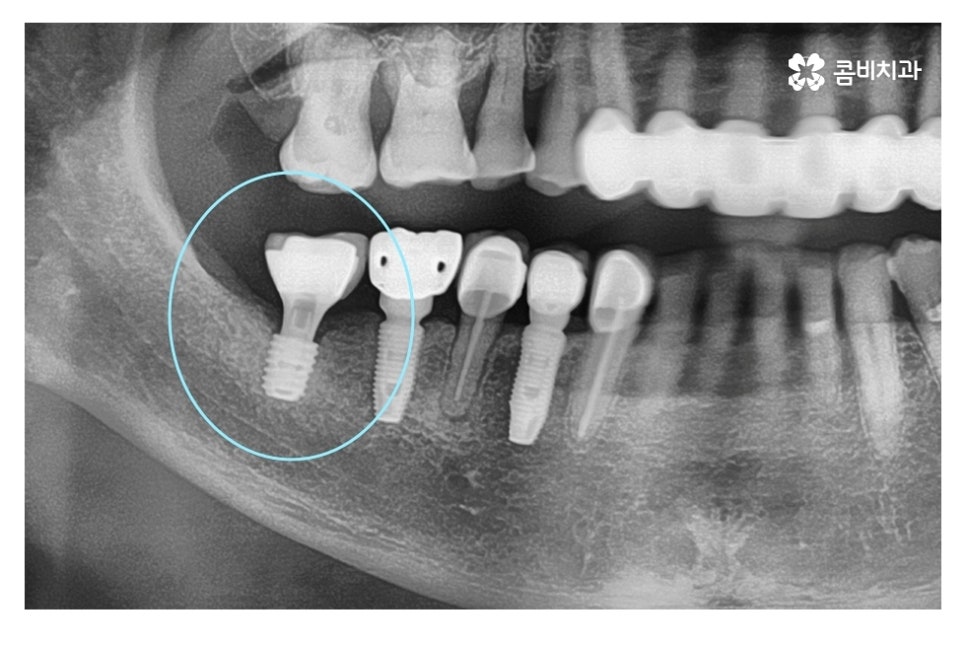

위 사진의 경우 인공치근이 골 유착 과정을 거친 후에 2차 수술 과정을

통해 임시고정 나사를 연결하여 잇몸 밖으로 노출시킨 과정이며

이 과정에서 원형의 임시고정 나사가 관찰이 되고 2차 수술 후에는

이곳을 청결하게 관리를 해주어야 잇몸이 잘 아물게 되실 수 있어요.